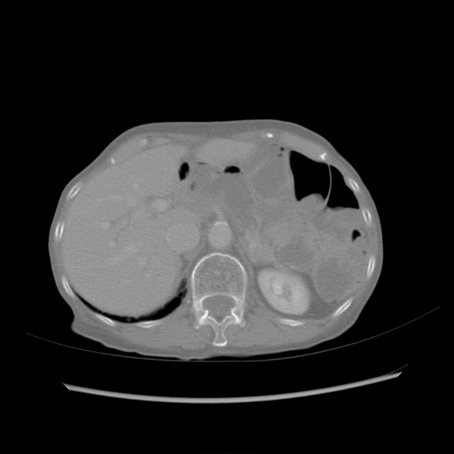

症例25(横断像)

【症例】80歳代女性

【主訴】胸のつかえ感

【現病歴】約9時間前に食後から胸のつかえた感じあり、嘔吐あり、来院。

【既往歴】胃癌(全摘)、胆摘、虫垂炎

【身体所見】心窩部に圧痛あり、反跳痛なし。

【データ】WBC 5700、CRP 0.05